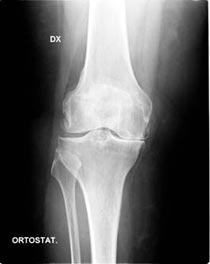

La malattia più frequente che colpisce il ginocchio è l’artrosi. E’ una patologia le cui cause non sono ancora del tutto chiare (viene infatti detta idiopatica) e fa sì che il manto cartilagineo in alcuni punti di maggior carico si usuri e si crei un attrito tra le due superfici ossee. Può colpire sia il compartimento mediale che quello laterale o, nei casi più severi, entrambi i compartimenti. E’ purtroppo una malattia progressiva ed irreversibile. L’artrosi può essere anche causata da una deformità assiale del ginocchio e/o dell’intero arto inferiore: avremo quindi il ginocchio varo (gambe a “O”) ed il ginocchio valgo (gambe ad “X”).